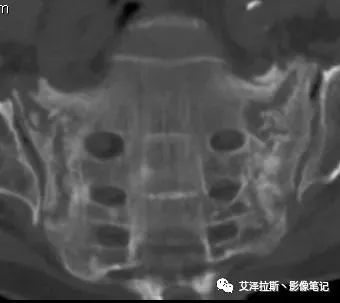

病例2:患者,女性,69岁,老年性骨质疏松症。

CT平扫:

X线、CT:骶骨重度骨质疏松,双侧骶骨翼皮质断裂,分别见迂曲走行的纵行透亮线位于骶孔外侧,大致与骶髂关节间隙平行,骨折端局部可见骨痂、骨质硬化。

骶骨功能不全骨折

①单侧或者双侧骶骨翼骨折,典型者呈“H”形,即“Honda征”;

②骨折线位于骶孔外侧(如下图,主要发生于1区),通常可能会伴随耻骨的功能不全骨折(如:病例2 右侧耻骨上支骨折,L5双侧横突骨折);

③愈合期骨折线模糊,骨痂形成,骨质硬化;